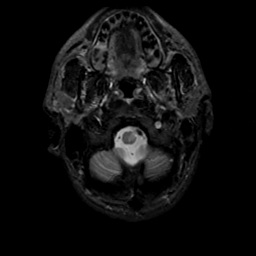

MR Study #20 October 6, 1991 -- Slice #3

[Home][Help][Clinical][Tour 1][Tour 2] Slice 3